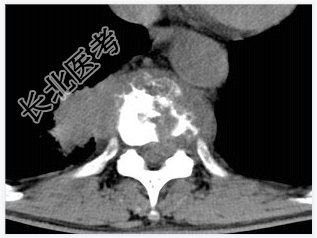

- [材料题] 男,32岁,低热、腰背痛,活动受限。

- 简答题1、结合CT检查,最可能的诊断是?